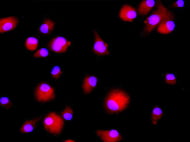

The Human Bone Marrow-Derived mononuclear cells are a mixed population of precursor cells with a single nucleus. The fraction includes monocytes, lymphocytes, as well as hematopoietic stem and...

Rat Bone Marrow Derived Mononuclear cells isolated from bone marrow, referes to a mixed population of cells that show regenrative and immunomodulatory potential. They are used in various...

Mononuclear cells isolated from bone marrow, referes to a mixed population of cells that show regenrative and immunomodulatory potential. They are used in various in vitro assays and...

Rat Bone Marrow Derived Mononuclear cells isolated from bone marrow, refers to a mixed population of cells that show regenerative and immunomodulatory potential. They are used in various...